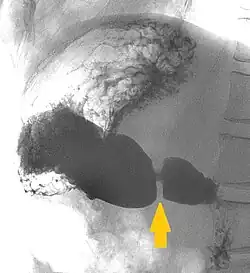

Der Pylorus (altgriechisch πυλωρός pylōrós, deutsch ‚Pförtner‘[1]), das Ostium pyloricum, der Magenausgang oder Magenpförtner ist der letzte Abschnitt des Magens zwischen dem Antrum pyloricum („Pförtner-Vorraum“) und dem Zwölffingerdarm (Duodenum). In seiner Wand bildet die ringförmig angeordnete glatte Muskulatur einen Schließmuskel, den Musculus sphincter pyloricus. Der Pylorus ist in Ruhe geschlossen. Er hat die Aufgabe, den Weitertransport des Nahrungsbreis vom Magen in den Darm zu regulieren.[2] Bei vielen Paarhufern weist der Pylorus durch Drüsen in der Submukosa und Verdickung der Ringmuskelschicht einen Wulst (Torus pylori) auf, der die Öffnung des Magenpförtners verengt.[3]

Bei leerem Magen ist der Pylorus entspannt. Die Regulierung der Öffnung und des Schlusses des Pylorus ist ein komplizierter und noch nicht in allen Aspekten verstandener Vorgang. Nicht jeder peristaltischen Welle des Magens folgt auch eine Pylorusöffnung. Der Energiegehalt der Nahrung, osmotischer Druck und pH-Wert in Magen und Zwölffingerdarm spielen dabei eine Rolle.[4] Die Magenentleerung wird dabei sowohl vom enterischen Nervensystem der Magenwand als auch vom Nervus vagus und verschiedenen Hormonen gesteuert. Flüssigkeiten und Nahrungspartikel kleiner als ein Millimeter passieren den Pylorus schnell, während gröbere Nahrungsbestandteile zurückgehalten und im Magen weiter verkleinert werden.[5]

Durch kurzzeitige Öffnung des Pylorus gelangt ein kleiner Anteil (Bolus) des Mageninhaltes (Chymus) in den Zwölffingerdarm. Der die Öffnung auslösende Pylorusreflex ist ein viszero-viszeraler Reflex, welcher den Muskel bei alkalischem (hoher pH-Wert) Chymus im Zwölffingerdarm schließt und ihn bei saurem oder fettem Chymus öffnet.[6] Gastrische Motilität bewirkt eine Leerung des Magens, während postprandiale Motilität darauf gerichtet ist, Nahrung zwischen den Mahlzeiten zurückzuhalten, um eine kontinuierliche Abgabe zu gewähren. Die gastrische Motilität spielt eine Schlüsselrolle bei den die Nahrungsaufnahme regulierenden Empfindungen von Sattheit, Hunger und Völlegefühl.[7]